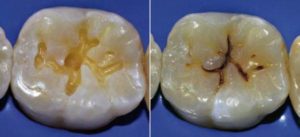

Приведенные картинки демонстрируют стадии формирования кариеса – от пятна до пульпита.

Фото демонстрирует, как выглядит кариес в различной стадии формирования. В зависимости от глубины полости гниения, различают поверхностное, среднее или глубокое кариозное поражение.

Фото — Стадия пятна Средний Глубокий кариес

- фиссурные – это разрушение зубов в фиссурах (фиссуры – естественные углубления, впадины между выступами на рабочей горизонтальной поверхности жевательных зубов (смотри фото);

Фото — Фиссурный кариес

Фото — Боковое межзубное разрушение, тёмные пятна на фото являются внутренними кариозными полостями